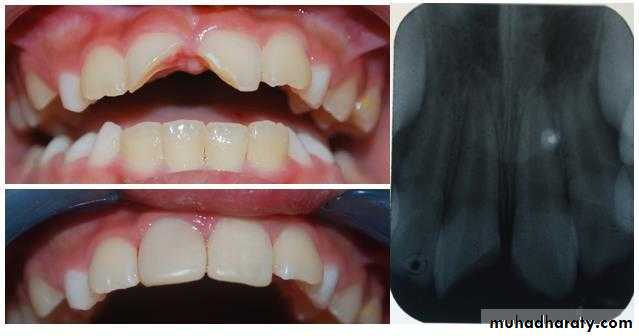

The procedure in which the small exposure of the pulp, encountered during cavity preparation or following a traumatic injuries or due to caries, with a sound surrounding dentin, is dressed with an appropriate biocompatible radiopaque base in contact with exposed pulp tissue prior to placing a restoration.

Small pin point mechanical pulp exposure of diameter less than 1mm .

Traumatic exposure in a dry , clean field which reported to the dental office within 24 hours ( without previous symptoms of pulpitis with normal radiographical finding ) .

Small pin point pulp exposure= 1mm